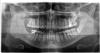

@maru77, @orthodontist Я мужа еще в воскресенье на кь отправляла. Я, а не врач.

Ни один из стоматологов не отправил на кт и не предложили это сделать.

Без кт и понимания, что именно положили в канал сложно давать оценочное суждение

Но обычно, когда каналы вскрыли, уже меньше болит

@ivy, а кт почему не сделали ?

Из прикуса зуб вывели ?